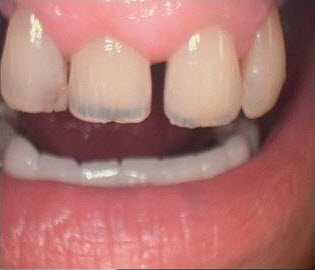

Worn Translucent Incisal Edges, Translucency Corrected with Hybrid Resins